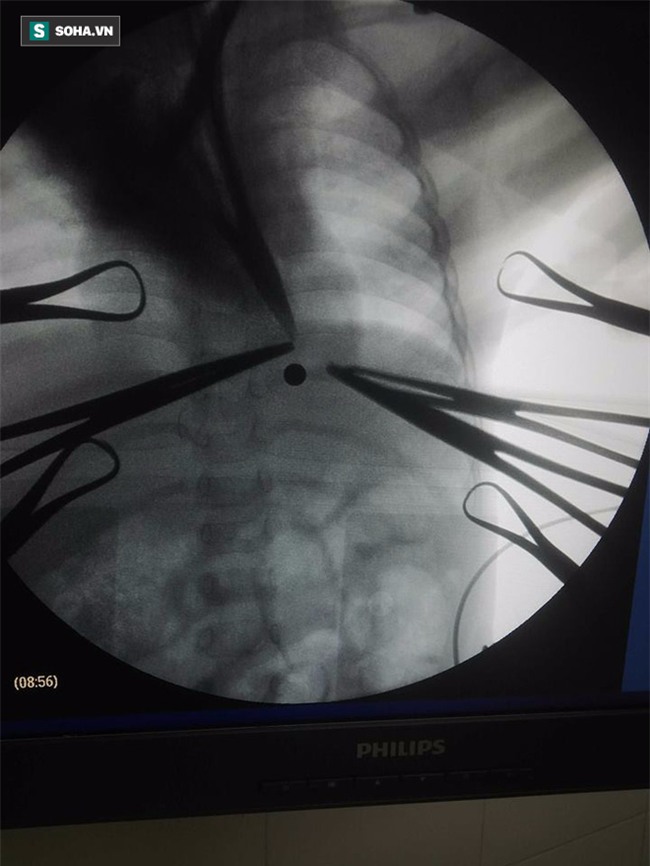

Tình trạng bệnh nhi khi nhập viện được Bác sĩ Thái Văn Bình - Trưởng khoa Chấn thương chỉnh hình - Bỏng Bệnh viện Sản nhi Nghệ An cho biết: "Hình ảnh chụp chiếu tại bệnh viện cho thấy viên đạn hình tròn đi xuyên từ ngoài vào tận phía trong ngực bệnh nhi, gây rách màng phổi, tình trạng hết sức nguy hiểm".

Sau khi hội chẩn liên khoa, các bác sĩ đã định vị viên đạn bằng màn hình tăng sáng C-ARM phát hiện dị vật cản quang và lấy ra viên đạn ra. Đây là phương pháp mổ lấy dị vật mới được ứng dụng tại Bệnh viện Sản - Nhi Nghệ An.